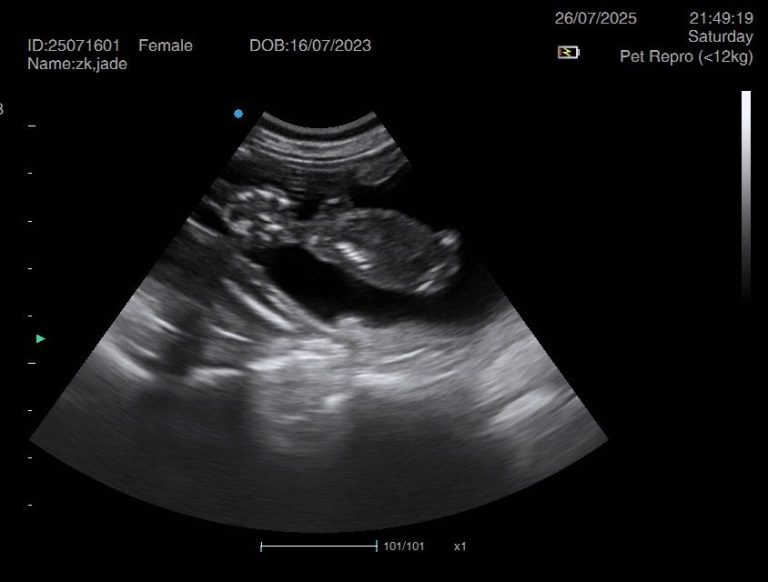

Ultrasound pregnancy scanning is a safe, non-invasive way to confirm pregnancy in dogs and cats, offering breeders and pet owners peace of mind and vital information to support responsible care. It allows us to detect gestational sacs, assess foetal development, and estimate litter size—all while ensuring the wellbeing of the animal.

Pregnancy can sometimes be detected as early as Day 18 post-mating, but scanning at this stage is not routinely recommended. Embryos are still developing and may not be clearly visible, and there is a natural risk of embryo resorption, which can lead to misleading or inconclusive results.

For the most accurate and reliable scan, we advise booking between Day 25 and Day 32, when pregnancy is more easily confirmed and foetal structures are clearer. If an early scan is performed and no pregnancy is detected, we offer a FREE complimentary re-scan after 7 days at the clinic to ensure clarity and support informed decision-making.

Our approach balances early insight with ethical care—always prioritizing the comfort of the animal and the accuracy of the results.

Gallery